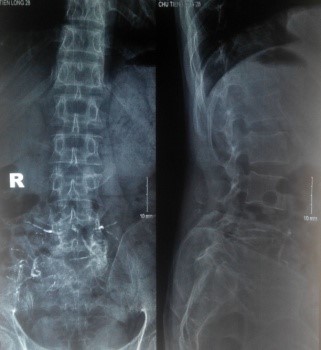

Trên X-quang, CT scanner khối u phá hủy vỏ xương gần hết thân và cuống sống L5.

Trên X-quang thường quy, u TBKL thường có các đặc điểm: u hình sáng, trung tâm khối u tăng thấu quang nhất và đậm độ cản quang tăng dần ra phía ngoại vi, đôi khi các bè xương cản quang bị cắt tạo thành hình nang lớn có nhiều vách ngăn (hình tổ ong hay hình bọt xà phòng). Tổn thương có thể phá hủy vùng vỏ xương kế cận song thường không phá hủy bề mặt khớp. Thường không có biểu hiện canxi hóa trong lòng khối u và không có phản ứng màng xương. Đặc điểm nang xương hình bọt xà phòng có thể nhầm với nang xương phình mạch nếu chỉ dựa vào x-quang để chẩn đoán [5,11,12]. Dựa vào hình ảnh x-quang, Campanaci (1987) đã chia u TBKL thành 3 độ:

- Độ I: U hình hủy xương có đường viền xương xơ đặc, vỏ xương nguyên vẹn, vỏ xương chưa bị phồng lên.

- Độ II: U có hình hủy xương giới hạn rõ nhưng không có đường viền xương xơ đặc, vỏ xương còn nguyên dù bị biến dạng phồng lên.

- Độ III: U hủy xương giới hạn không rõ, vỏ xương bị phá vỡ và xâm lấn vào phần mềm.

Độ tổn thương trên X-quang phản ánh tình trạng hoạt động của khối u, yếu tố quan trọng cho việc chỉ định phương pháp điều trị và tiên lượng. Độ cao phản ánh sự phá huỷ xương mạnh, điều trị khó khăn, nguy cơ tái phát cao [13].